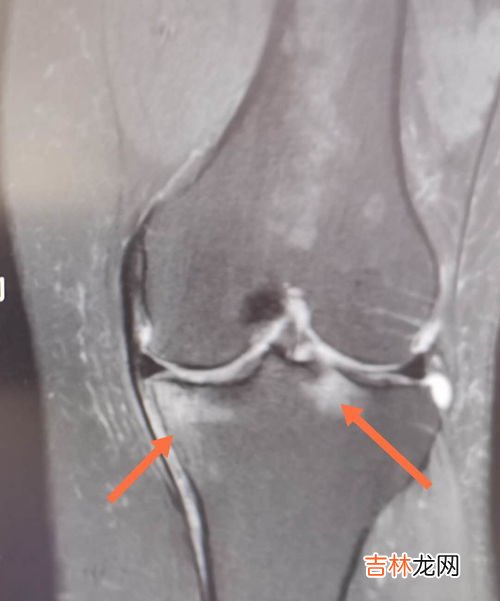

第一名:膝盖

膝盖损伤占所有运动损伤的55%,涉及的运动包括跑步、自行车、游泳、足球、篮球、排球等 。建议:应经常更换运动鞋及鞋垫;运动场地要软一点;多进行锻炼四头肌的力量练习;膝盖一旦感觉不适 , 至少休息两天,可以服用一些抗炎药物 。